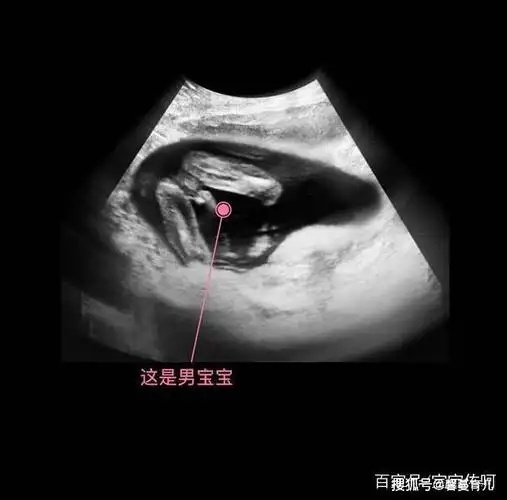

胎儿从卵泡到性别形成17张图片清晰诠释男宝女宝看得很清楚